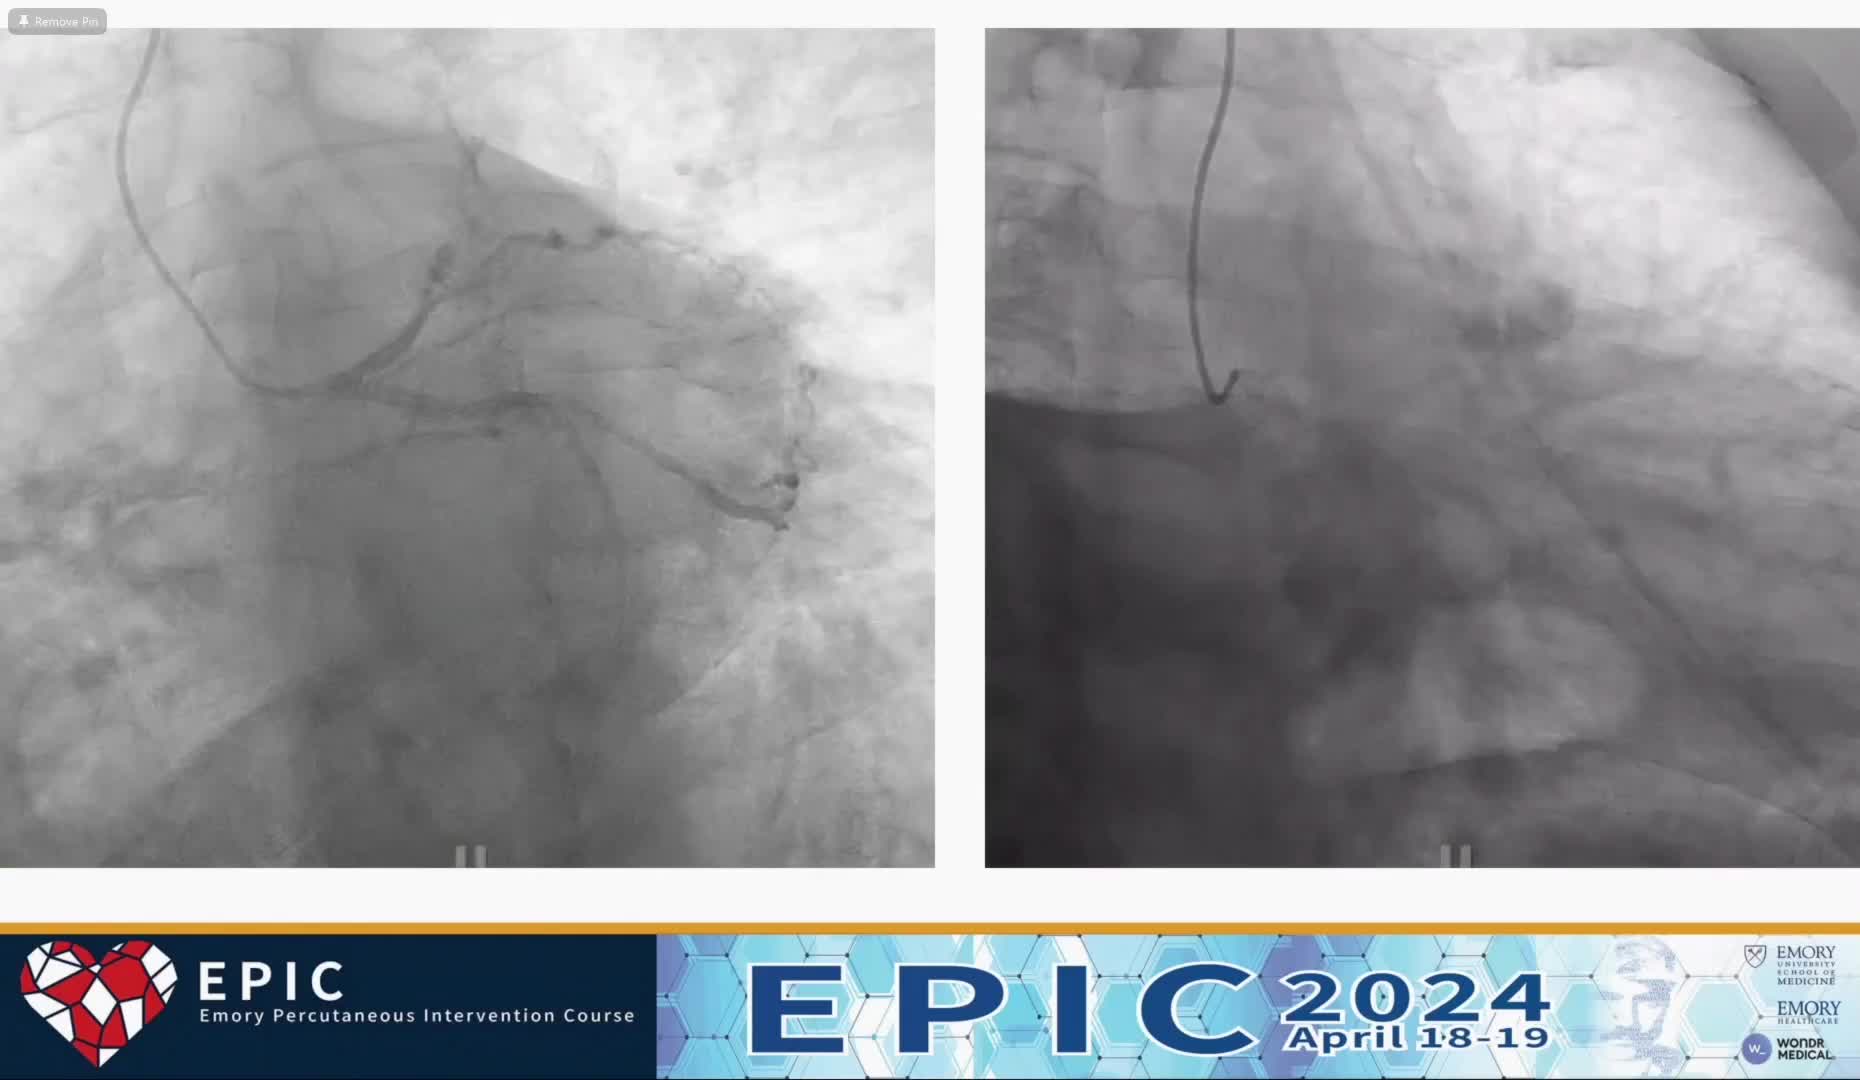

Practical tips and tricks for IVUS measurements